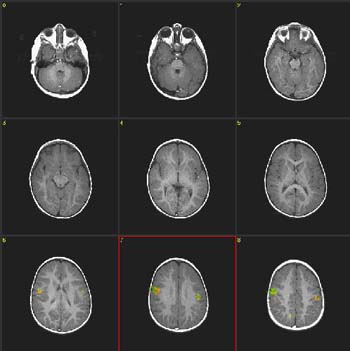

| Imagen |

| Activación |

Se observa una activación bilateral en las caras parasagitales de los lóbulos frontales, que es mayor en el lado derecho. El área auditiva primaria está activada en el lado izquierdo. También hay activación dispersa en el lóbulo parietal derecho. Se observa activación bilateral en el cúneo y precúneo del lado izquierdo. |